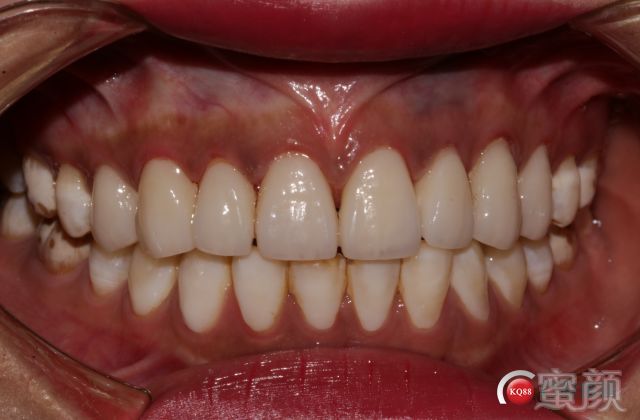

戴临时牙的情况;颜色选择略黄;和最终修复体对比后患者更容易接受。

唯一的调整是因为去除树脂后切端的牙体发黑所以从开窗式的修复方案改为对接式。包绕式。

粘接式非常痛苦的过程~~~省略一万个字,上橡皮章排龈,非常费时。

两周后再拍一下效果和大家一起讨论。多多指教;没有对比就没有伤害;切端通透生长叶形态能表达出来;牙面纹路生动符合患者年龄的纵横纹的表达。面型笑线和牙体的协调。